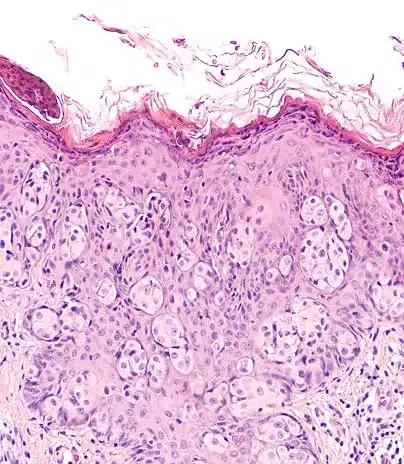

Diagnóstico por Imágenes y Biopsia

Diagnóstico Sin Cirugía

• La biopsia core de mama (con aguja gruesa) es el método de elección frente a la aspiración con aguja fina (BAAF) o a la cirugía diagnostica (biopsia quirurgica)

• La triple evaluación (clínica, imagen y biopsia) debe ser la norma para confirmar el diagnóstico.